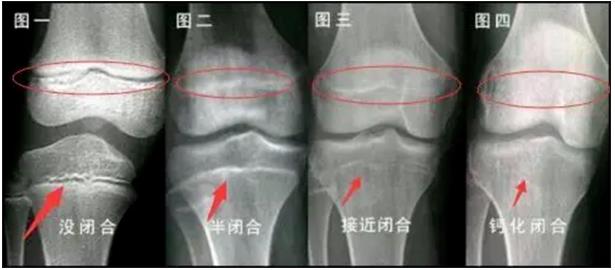

키가 쑥쑥 크는 3개의 쾌속성장기, 잘 틀어쥐여야

중산대학 손일선기념병원 소아과 부주임, 소아과신경내분비전문과 주임 량립양은 일반적으로 아이들의 성장발달이 모두 다르지만 기본적인 법칙이 있다고 밝혔다. 일반적으로 아이의 키성장은 3개 단계가 있는데 태여나서부터 2살까지가 영...

아이 골밀도가 낮은 것은 칼시움부족 때문일가?

골밀도는 뼈내 칼시움 침착정도를 나타내지만 어린이와 성인이 골밀도가 낮다는 개념은 완전히 부동하다.왕성한 성장기의 아이들은 뼈가 계속 늘어나고 두꺼워지면서 뼈성장을 촉진하는 호르몬이 증가하기에 칼시움질이 낮아지고 골밀도가 따...